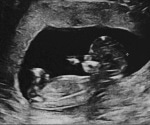

Predicting kidney abnormalities in utero with deep learning